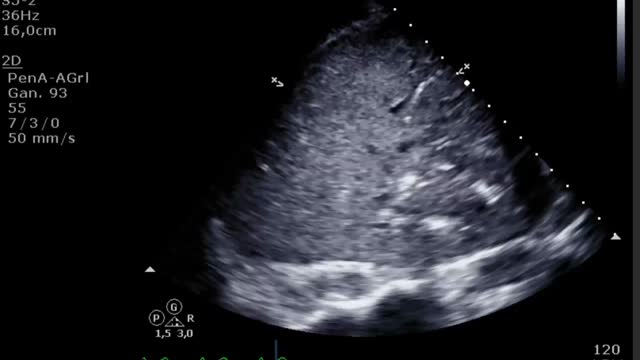

Durante la canulación, mediante la ecografía, podremos comprobar la inserción intravascular de las guías y posterior de las cánulas. En caso de uso de cánula de doble luz es indispensable la ETE, ya que puede haber complicaciones graves durante su implante (perforación de la AD o cava superior, migración al VD) y se debe comprobar una correcta orientación del flujo de retorno hacia la válvula tricuspídea21. En canulación con doble cánula simple, puede utilizarse la ETT o la ETE en ausencia de una buena ventana acústica. En la configuración fémoro-yugular, la cánula de drenaje debe quedar en la cava inferior por debajo de la vena suprahepática izquierda y el extremo de la de retorno a nivel de la AD (fig. 2) (suplementario 3). En la configuración fémoro-femoral, la cánula de drenaje debe quedar en la cava inferior y la de retorno en la AD. La distancia entre ambas cánulas debe ser al menos de 10cm para evitar la recirculación.

Canulación e inicio del soporte veno-arterialLa evaluación, la punción vascular y la colocación de guías es común a la VV y debemos seguir la misma sistemática. Respecto al posicionamiento de la cánula venosa, en la VA esta debe ser multiperforadora y se debe colocar a la altura de la AD con el extremo a nivel de la vena cava superior para tener el mayor drenaje posible (suplementario 10).